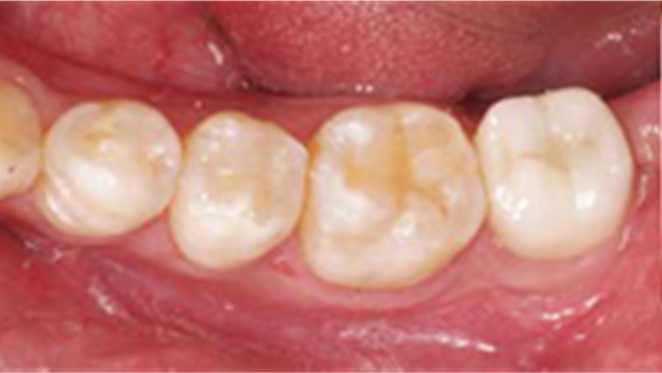

“AnyOne implant system guarantees

excellent aesthetics & functionality for any implantologist

& any patient. ”

Clinical case: Single molar implant with bone augmentation

- Courtesy of Dr. Jung Sam Lee, Korea -

Keywords

AnyOne, bone augmentation, osteotomy socket, peri-implant tissue, autogenous bone, GBR, single replacement, Auto-Max, Dr. Jung Sam Lee

Products:

AnyOne implant system, Auto-Max